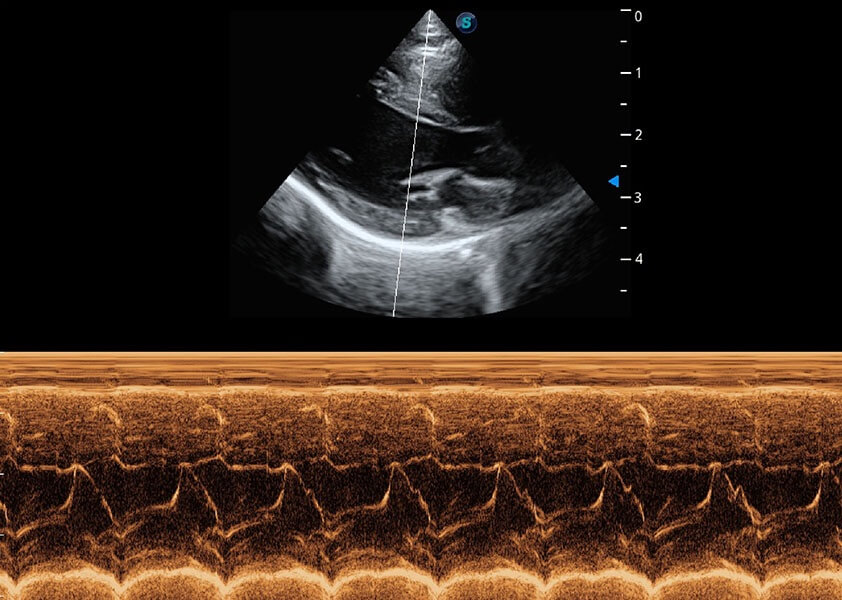

(犬)四腔心血流

(猫)二尖瓣M型